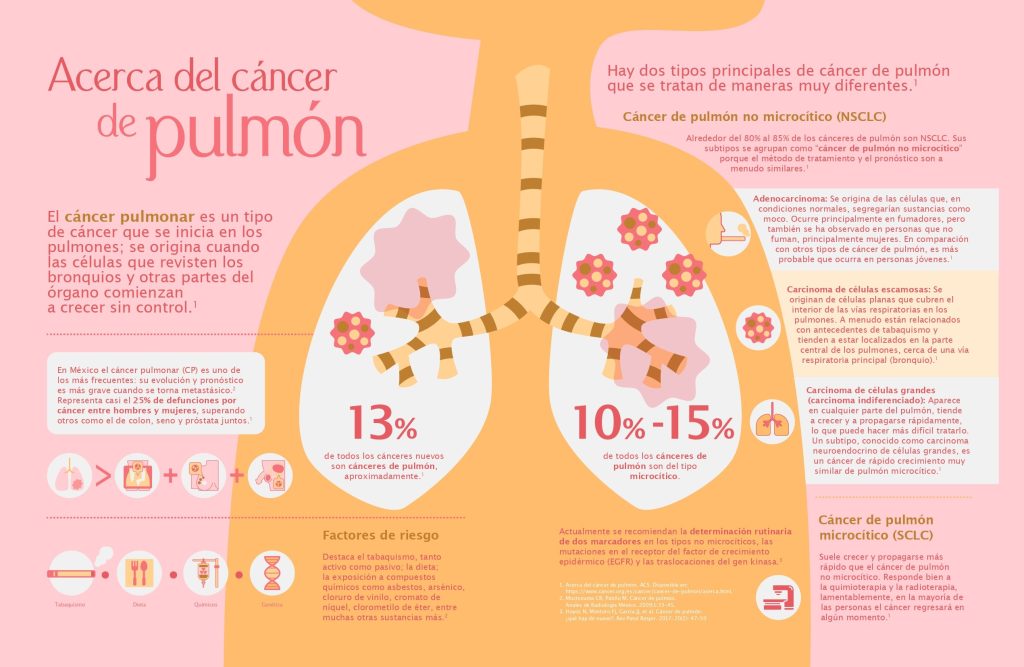

Respirando con Valor, a través de su directora institucional, llamó a evitar normalizar síntomas respiratorios, invitó a informarse sobre el cáncer de pulmón, evitar la automedicación, adoptar estilos de vida saludables, pero sobre todo “terminar con el estigma de que es una enfermedad que únicamente afecta a fumadores, ya que si bien es un factor de riesgo importante, existen otros como la exposición al humo de leña y a los ambientes de contaminación atmosférica elevada y la exposición a sustancias tóxicas que se encuentran en los lugares de trabajo o en el medio ambiente también pueden llevar a un cáncer de pulmón”.

Datos de un estudio realizado por el Instituto Nacional de Enfermedades Respiratorias (INER), alrededor de 40% de los cánceres pulmonares en México ocurrieron en personas no fumadoras, la causa se atribuyó a la exposición al humo de leña.[5]